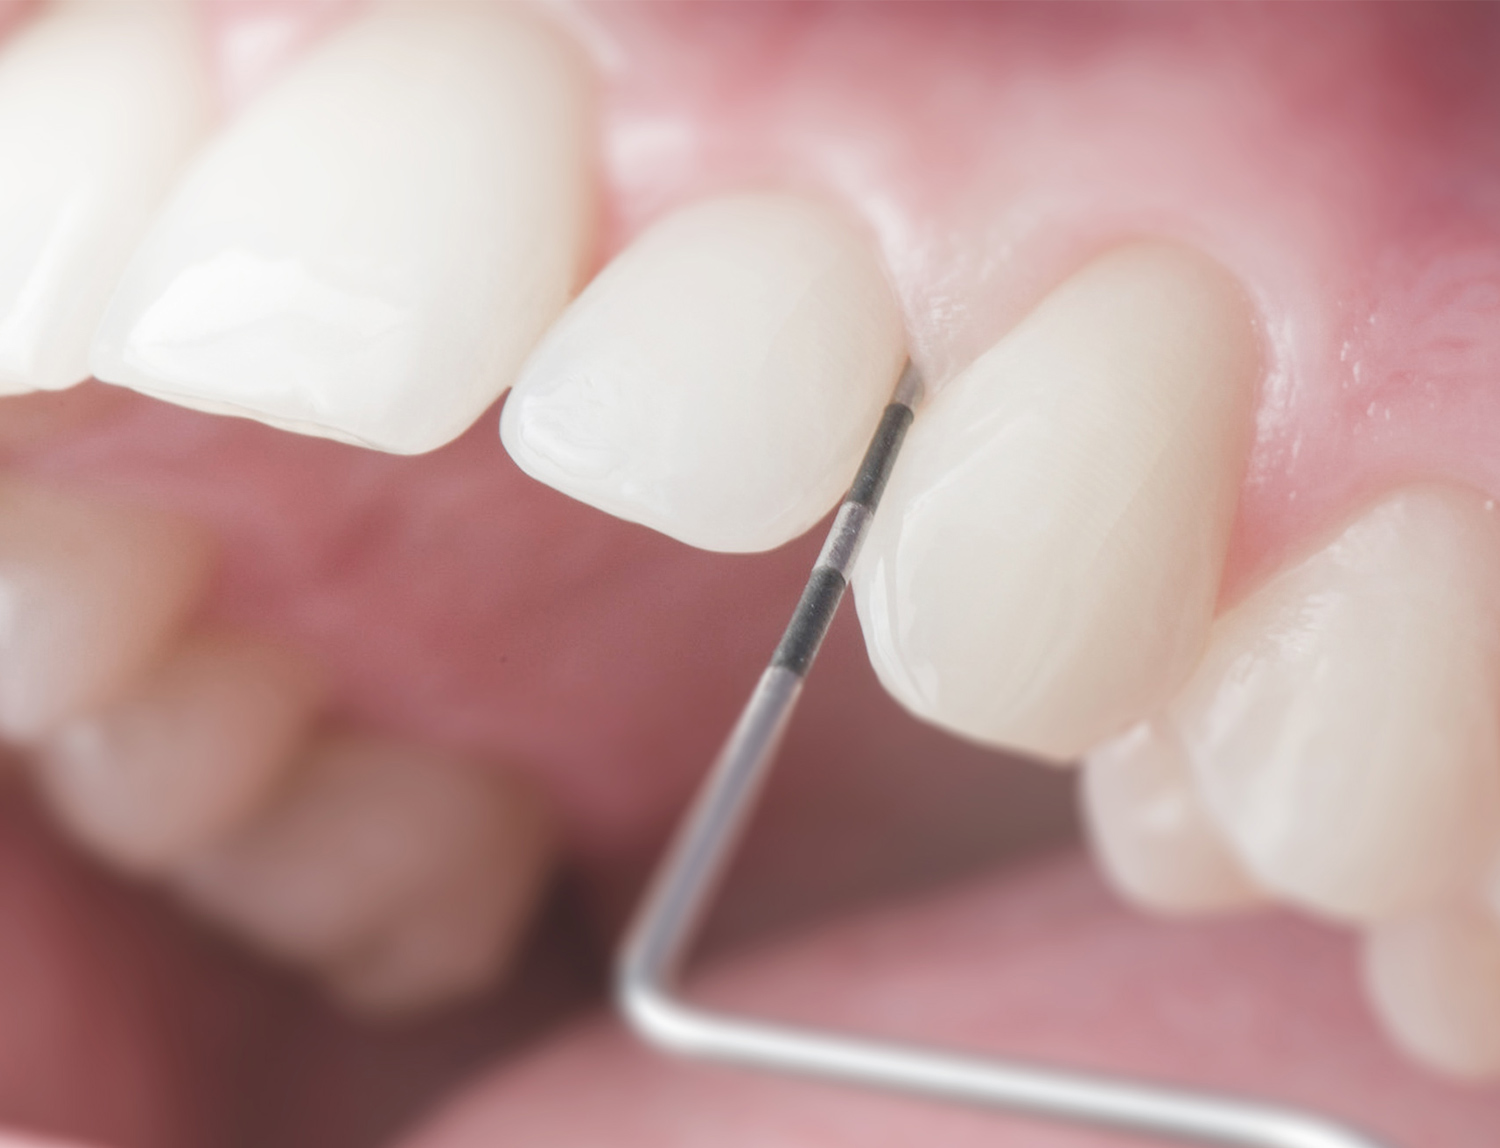

Prophylaxe und Dentalhygiene

Eine gute Mundhygiene, die regelmässige professionelle Zahnreinigung und die Kontrolle durch Zahnärzte und Dentalhygienikerinnen bieten den besten Schutz vor Zahn- und Zahnfleischerkrankungen. Die Gesundheit Ihres Mundraums ist uns wichtig. Regelmässige und individuell auf Sie abgestimmte Recall-Intervalle und ein von unseren qualifizierten Dentalhygienikerinnen optimal zusammengestelltes Mundhygieneprogramm sind dabei entscheidend.